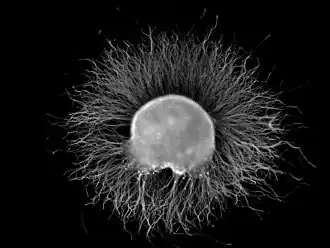

A dorsal root ganglion (DRG) from a chicken embryo (around stage of day 7) after incubation overnight in NGF growth medium stained with anti-neurofilament antibody. Note the axons growing out of the ganglion.